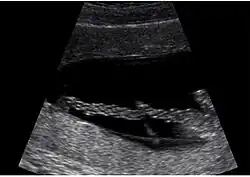

Die menschliche Nabelschnur ist bei einem Reifgeborenen etwa 50–60 Zentimeter lang, 1,5–2 Zentimeter im Durchmesser, meist spiralig gewunden und vom Amnion umgeben. Sie enthält anfänglich vier Blutgefäße, von denen sich die rechte Nabelschnurvene zwischen dem 28. und 32. Tag der Embryonalentwicklung zurückbildet. Danach verfügt die Nabelschnur in der Regel über drei Gefäße, zwei Nabelarterien (Arteriae umbilicales), die kohlenstoffdioxidreiches und nährstoffarmes Blut vom Kind zur Plazenta leiten, und eine Nabelvene (Vena umbilicalis), die Blut von der Plazenta zum Kind leitet. Typisch für die Nabelschnur ist das gallertige Bindegewebe, das einerseits für die notwendige Flexibilität verantwortlich ist und gleichzeitig vor einem Abknicken bei Biegebelastungen schützt. Es besteht aus feinen Kollagenen, wenigen Fibroblasten und großen Mengen an wasserbindenden Hyaluronen (Wharton-Sulze).

Ist nur eine Nabelarterie nachweisbar, spricht man von singulärer Umbilikalarterie. Eine solche Nabelschnur mit zwei statt drei Gefäßen tritt beim Menschen als seltene Variante auf (circa ein Prozent); hierbei ist das statistische Risiko einer Fehlbildung an anderen Organen um den Faktor 1,3–1,6 erhöht.[1] Auch kurze Nabelschnüre gehen mit einem erhöhten Risiko von Fehlbildungen einher; beispielsweise können die Bewegungen des Föten reduziert sein infolge von Störungen des zentralen Nervensystems oder der Muskulatur.[2] Bei langen Nabelschnüren ist das Risiko für einen Knoten oder ein Vorfallen der Nabelschnur erhöht.[2]